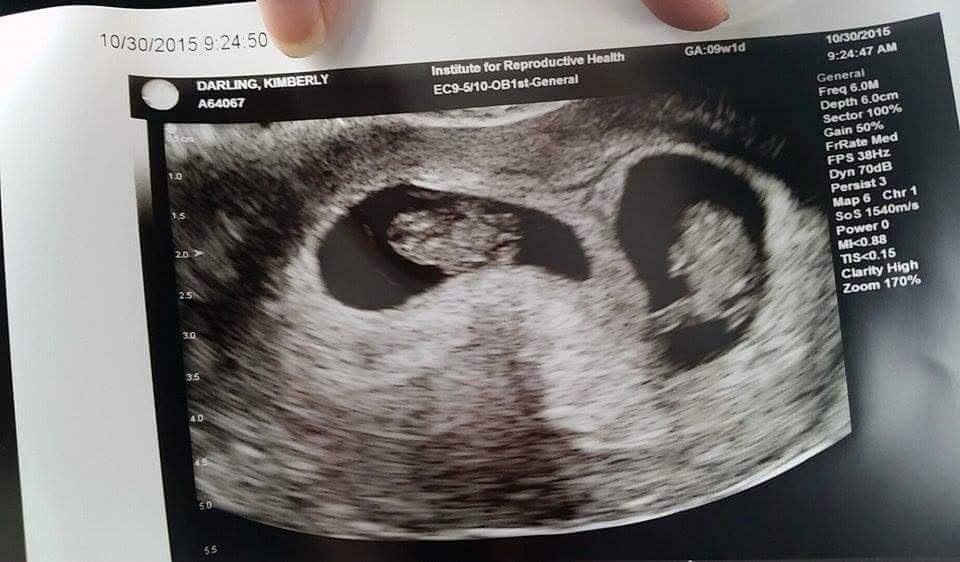

Had my dating u/s last night at 9w2d. Here's my little baby! We got to see the heart flicker! Heartbeat was 176 and they said s/he looks healthy. What an exciting experience that was!!!